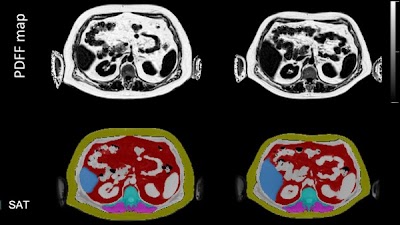

Evaluating Sex-specific Differences in Abdominal Fat Volume and Proton Density Fat Fraction on MRI Scans Using Automated nnU-Net-based Segmentation doi.org/10.1148/ryai.2… Mingming Wu BMRR #nnUNet #ML #MachineLearning

Evaluating Sex-specific Differences in Abdominal Fat Volume and Proton Density Fat Fraction on MRI Scans Using Automated nnU-Net-based Segmentation doi.org/10.1148/ryai.2… <a href="/MingmingWu10/">Mingming Wu</a> <a href="/BMRRgroup/">BMRR</a> #nnUNet #ML #MachineLearning